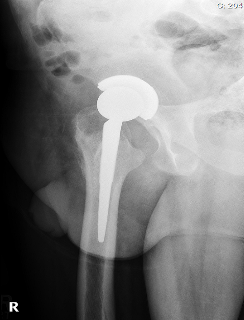

Total hip replacement was the treatment of choice for this case taking into consideration the poor bone stock available after removal of the metalwork and high risk of avascular necrosis which would have compromised the outcome of revision ORIF or a valgus osteotomy. This was the consensus at a multi-disciplinary meeting including the trauma surgeon who performed the initial operations, hip preservation surgeons who specialise in various osteotomies, and arthroplasty surgeons.

Postoperative radiographs were satisfactory: